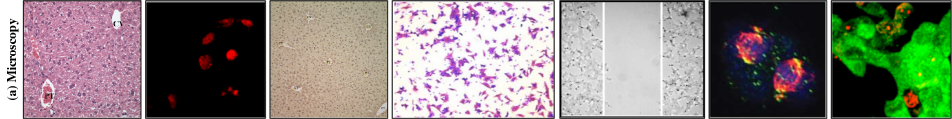

We classify the images from the previous collection step into four categories — (1) Microscopy (2) Blots/Gels (3) Flow-cytometry or Fluoroscence-activated cell sorting (FACS) and (4) Macroscopy. This taxonomy is made considering both the semantics and visual similarity of different image classes. Semantically, microscopy includes images from experiments that are captured using a microscope. They include images of tissues and cells. Variations in microscopy images can result from factors pertaining to origin (e.g. human, animal, organ) or fluorescent chemical staining of cells and tissues. This produces images of diverse colors and structures. Western, northern and southern blots and gels are used for analysis of proteins, RNA and DNA respectively. The images look similar and the specific protein or blot types are visually indistinguishable. FACS images look similar to synthetic scatter plots. However, the pattern is generated by a physical experiment which represents the scattering of cells or particles. Finally, Macroscopy includes experimental images that are visible to the naked eye and do not fall into any of the first three categories. Macroscopy is the most diverse image class with images including rat specimens, tissues, ultrasound, leaves, etc. Table 1 shows the composition of BioFors by image class. Figure 2 shows inter and intra-class diversity of each class. The image categorization discussed here is easily learnable by popular image classification models as shown in Table 2.